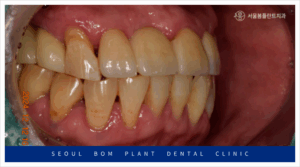

임플란트와 잇몸뼈가

단단히 결합되기를 충분히

기다린 뒤 아래턱 양측 먼저

임플란트 보철물 제작을 진행하였으며,

최종 보철물은

자연치아와 강도가 유사하고

심미적인 지르코니아 보철물로

마무리해 드렸습니다.

위턱의 양측 어금니 부위도

충분한 시간이 지난 뒤

보철물 수복을 위한

인상채득을 진행하였으며,

아래턱과 같이

지르코니아 보철물로